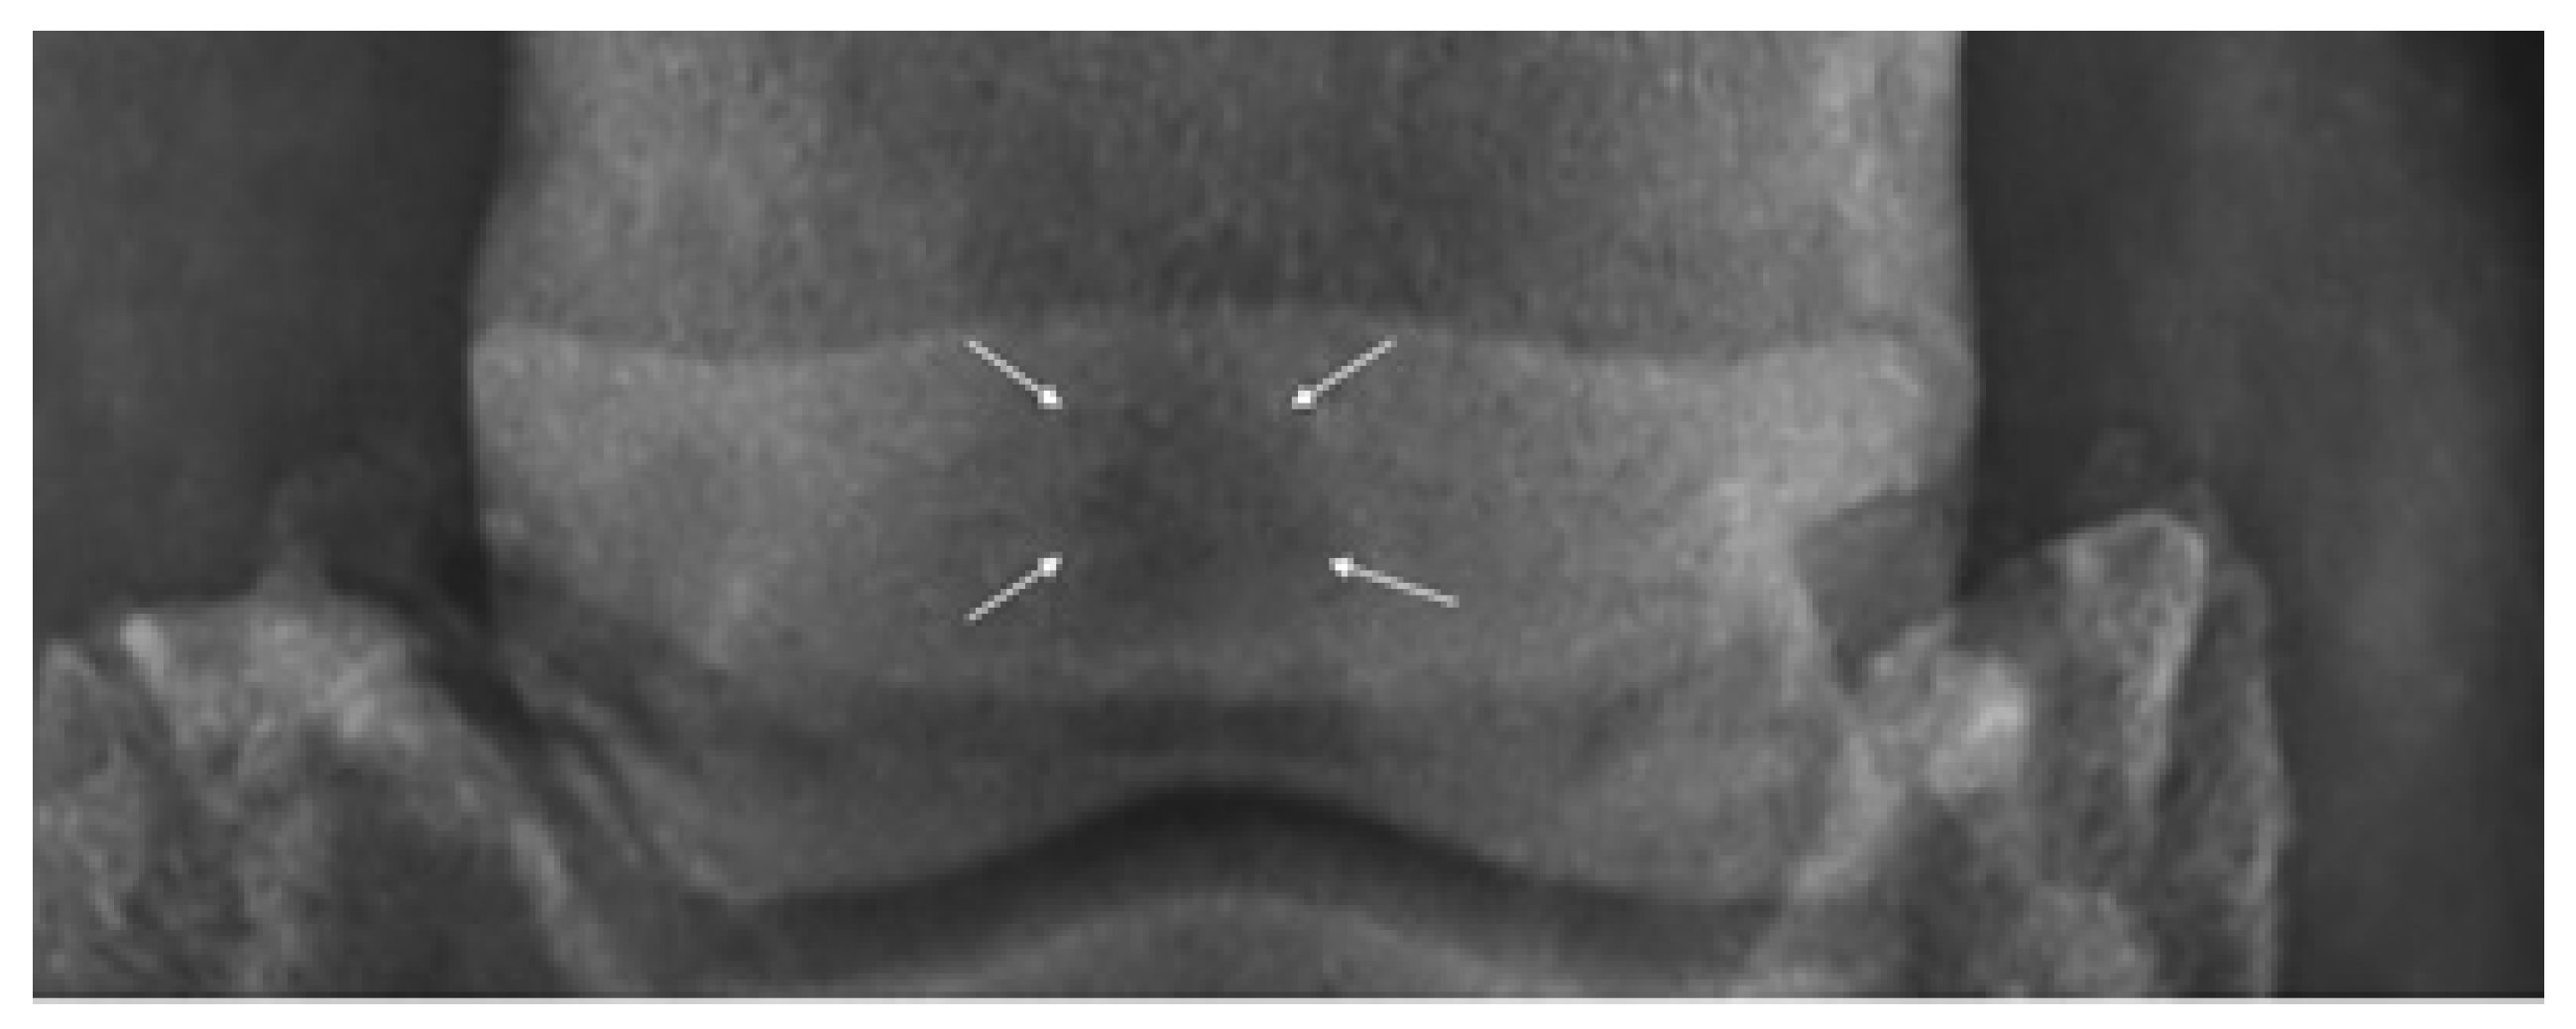

In addition, 65° DPr-PaDiO radiographs of the hooves were taken for each of the horses included in the study group, revealing enthesophytes on the medial and lateral aspects of the navicular bone in three of the horses, along with increased medullary sclerosis of the navicular bone in four horses (Figure 2), while PaPr-PaDIO radiographs revealed sclerosis of the medullar cavity in two horses and increased opacity on the flexor border of the navicular bone for three horses. The LM revealed erosions of the flexor cortex of the navicular bone for two horses. Multiple lesions were observed in the case of six horses, and in only two horses did we observe a singular lesion [20]. The radiographic images were read by a veterinarian radiologist with 7 years of experience in the equine field.

Figure 2.

Horses with palmar foot pain: DPr-PaDiO radiolucent area (sclerosis of the medullary cavity) in the navicular bone (white arrows).